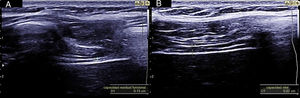

La medición del grosor diafragmático es otro método actualmente empleado, permite determinar la masa muscular diafragmática, y valorar la fracción de engrosamiento, o «thickening fraction» (TF). Para esta medición se utiliza una sonda lineal de alta frecuencia, colocada entre los últimos espacios intercostales. De esta forma se localiza la «zona de aposición», donde el diafragma se inserta en la pared costal. El diafragma se identifica como la franja hipoecogénica limitada por dos líneas hiperrefringentes, que corresponden a la pleura y al peritoneo. El TF es la relación entre el grosor en reposo (capacidad residual funcional) y en máxima inspiración (capacidad vital) (figs. 1 y 2).